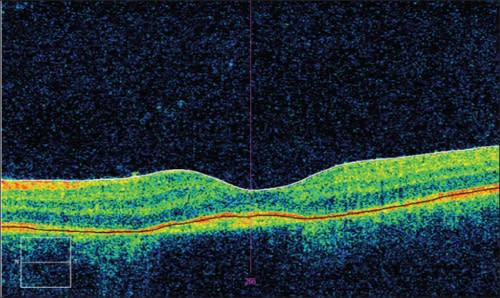

Optical coherence tomography (Cirrus HD-OCT, Carl Zeiss Meditec, Dublin, CA) demonstrated prominent subretinal fluid and intraretinal cystoid spaces within the left macula and a central foveal thickness of 440 µm (Figure 1).

Figure 1. OCT (Cirrus HD-OCT, Carl Zeiss Meditec, Dublin, CA) shows prominent subretinal fluid and intraretinal cystoid spaces within the left macula. Central foveal thickness was 440 µm; visual acuity was 20/400 eccentrically.